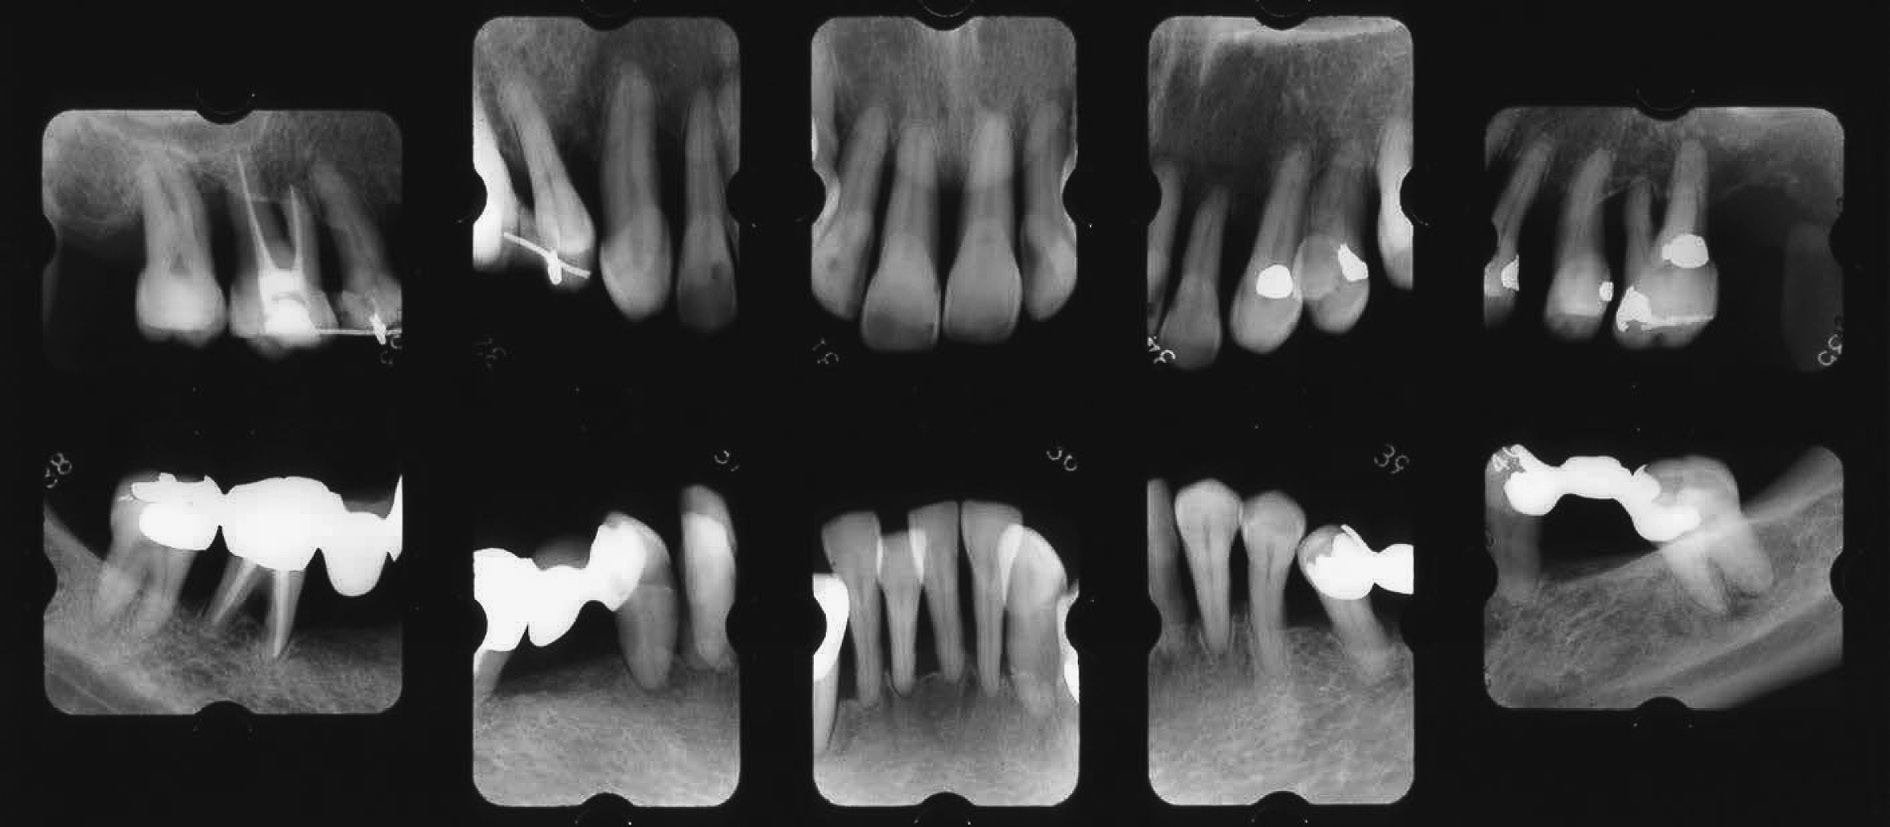

c) 治療経過とSPT重度の広汎型慢性歯周炎患者の初診時の病態写真(図7)とエックス線写真(図8)で,病態写真は一部紛失している。近隣歯科医の下でプラークコントロールや縁上スケーリング処置は受けたものの,外科処置やリコールの設定がなされなかったものである。高度な歯周組織破壊と著しい歯肉退縮が特徴である。ただ,動揺の揺れ幅や安定性に関しては頬舌方向の揺れより近遠心方向の揺れが明らかに少ない。14,35,44,45に歯の欠損があるものの,歯列の連続性が保たれていて,咬合圧等の外力に連座して抵抗できていたものと考える。そこで,二次性咬合性外傷への対策およびブラッシング時の機能的動揺への不安軽減を考慮して,計画の最重要点として,①隣接面を共有する全歯への暫間固定(前歯B-スプリント,臼歯A-スプリント),②欠損部への暫間義歯の装着の2つを掲げて処置を継続した。プラークコントロールは常時良好で,PCR値は10%前後に落ち着いていた。

歯周基本治療終了時の再評価で,初診時のエックス線写真像(図8)と比較して,歯槽骨の明らかな再生と骨の安定化傾向がみられた(図9)。さらに,15,16および24,25,26のA-スプリント,さらに13,12,11,21,22,23,24のB-スプリントは,二次性咬合性外傷の予防対策として暫間固定としての役割を十分に果たしていると考えられたので,それらは除去されることなく延長しての役割,すなわち,永久固定の補綴物間の補助的接着効果を期待して,形態修正および補強(レジンの追加)を施した。

SPT2年後の病態写真(図10)およびエックス線像(図11)である。歯槽骨のいっそうの再生と骨全体の安定化傾向が認められる。

初診時のエックス線写真(51歳,女性)。

歯周基本治療終了時のエックス線写真(初診より1年5ヶ月後)。